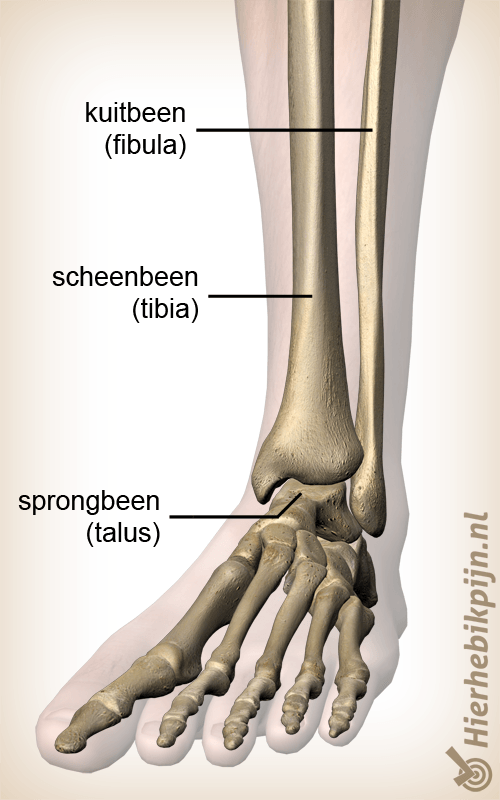

Enkel